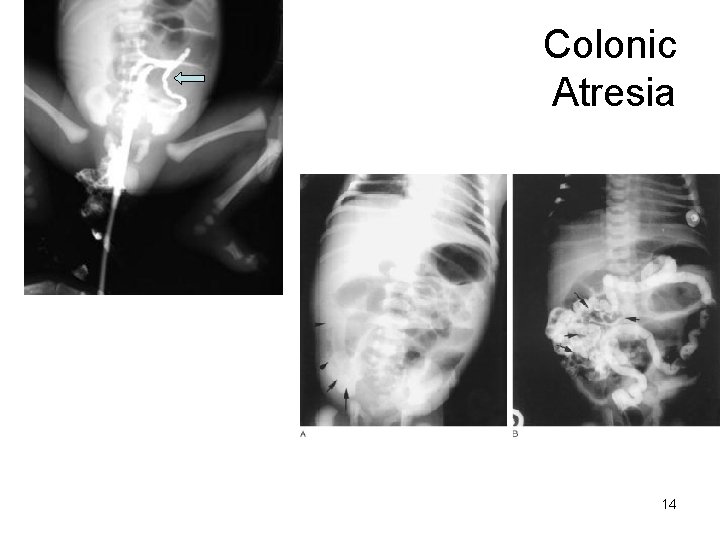

Colonic Atresia 14

Colonic Atresia 1. Congenital failure of development of the ________ 2. Frequent complication includes fistula formation to the genitourinary system 3. Must be repaired surgically 15